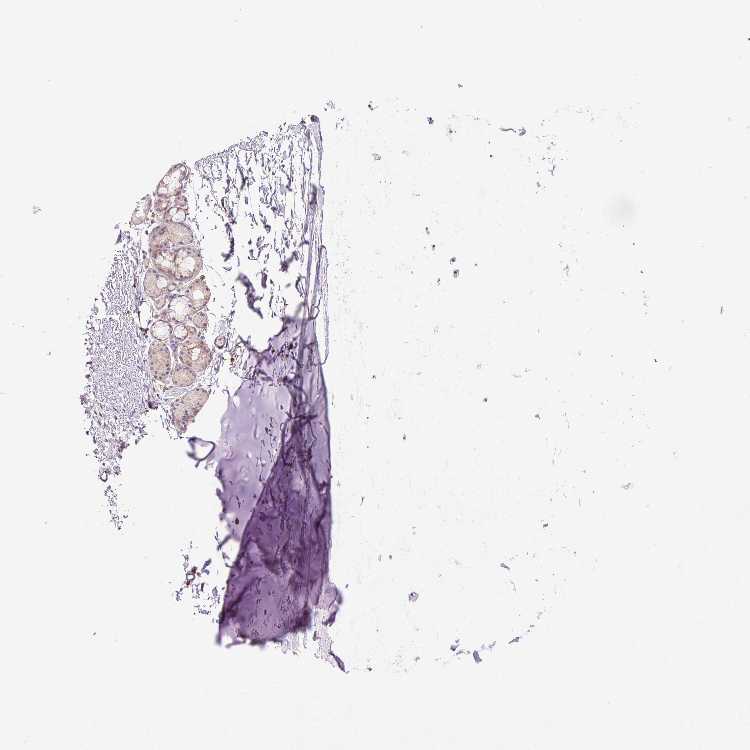

SOFT TISSUE 1 - Antibody stainingi

Antibody staining in the annotated cell types in the current human tissue is reported as not detected, low, medium, or high, based on conventional immunohistochemistry profiling in selected tissues. This score is based on the combination of the staining intensity and fraction of stained cells.

Each image is clickable and will lead to virtual microscopy that enables deeper exploration of all samples and also displays staining intensity scores, fraction scores and subcellular localization as well as patient and tissue information for each sample.

Antibody HPA053873

Chondrocytes Not detected

Fibroblasts Low

Peripheral nerve Not detected